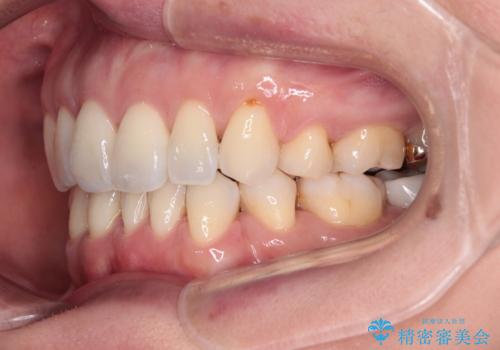

- 前方に飛び出した前歯を気にして来院された患者様です。

通常であれば上下左右の第一小臼歯4本を抜歯して口元の突出感を改善しますが、下顎前歯が1本欠損しており、上下の歯の数がアンバランスであるため、4本抜歯するかどうか悩むところでした。

上顎前歯はやや小さめで、下顎前歯はやや大きめであったため、上下左右4本を抜歯しても左右奥歯の咬み合わせは理想に近い状態を達成できると判断し、上下左右の第一小臼歯4本を抜歯し、ワイヤー装置にて矯正治療を行うこととしました。